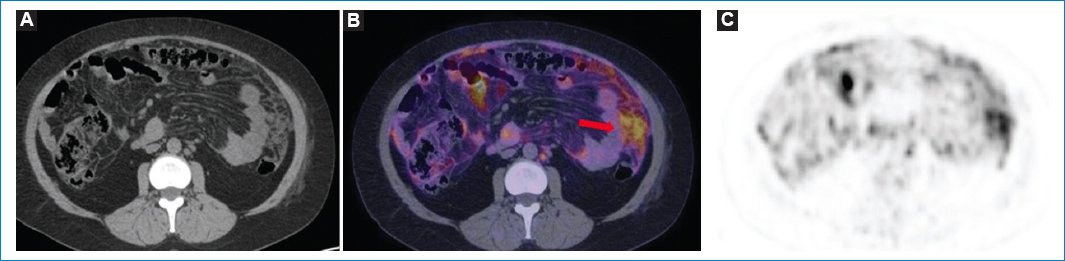

• –Un patrón difuso, con avidez por la 18F-FDG en forma difusa por el omento mayor y la superficie peritoneal (Figs. 811)

Figura 4. Mujer de 49 años con diagnóstico de linfoma no Hodgkin y LP. TC sin contraste endovenoso en imagen axial (A) que muestra patrón de engrosamiento nodular del peritoneo y adenopatías retroperitoneales. Fusión PET-TC (B) y MIP (C), cortes axiales, que demuestran el hipermetabolismo de los nódulos peritoneales y de las imágenes ganglionares (flecha).